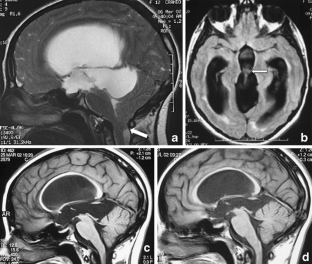

The sylvian aqueduct is the most common site of intraventricular blockage of the cerebro-spinal fluid. Clinical aspects, neuroradiological appearance, and treatment of hydrocephalus secondary to aqueductal stenosis are specific.

The correct interpretation of the modern neuroradiologic techniques may help in selecting adequate treatment between the two main options (third ventriculostomy or shunting). In the last decades, endoscopic third ventriculostomy has become the first-line treatment of aqueductal stenosis; however, some issues, such as the cause of failures in well selected patients, long-term outcome in infant treated with ETV, and effect of persistent ventriculomegaly on neuropsychological developmental, remain unanswered.